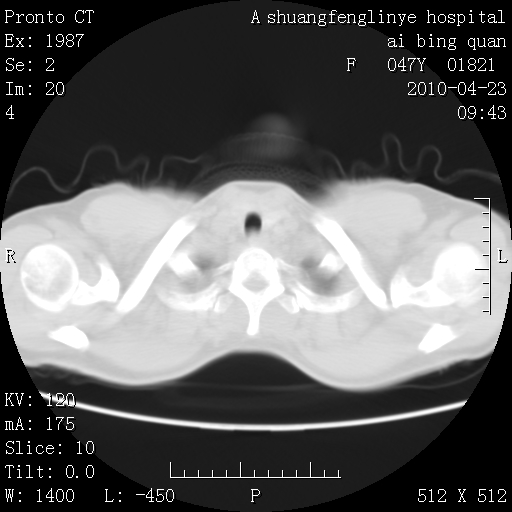

标题: CT25944:胸痛、气短、前几日高烧!肺Ca?请会诊! [打印本页]

标题: CT25944:胸痛、气短、前几日高烧!肺Ca?请会诊!

左侧乳腺低密度灶